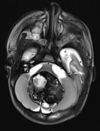

Qual o padrão da imagem na AMS-C?

Atrofia de cerebelo (vermis) e tronco (principalmente ponte); Hipersinal T2 na ponte: Sinal da cruz na ponte (não patognomônico), perda da barriguinha da ponte, Hipersinal nos pedúnculos cerebelares médios;

Atrofia de múltiplos sistemas tipo C

Quais são os tipos de AMS?

AMS tipo Putaminal (P) \*predominio de sintomas parkinsonianos e tipo Cerebelar (C) \*predominio de sintomas cerebelares

Atrofia da ponte e dos pedúnculos cerebelares médios Atrofia de múltiplos sistemas

Atrofia do putame, com hipossinal em T2 e GRE (em relação ao globo palido e nucleo rubro) e com uma faixa posterior de hipersinal (em aparelhos 1.5 T \*Pode ser normal em aparelhos 3 T).